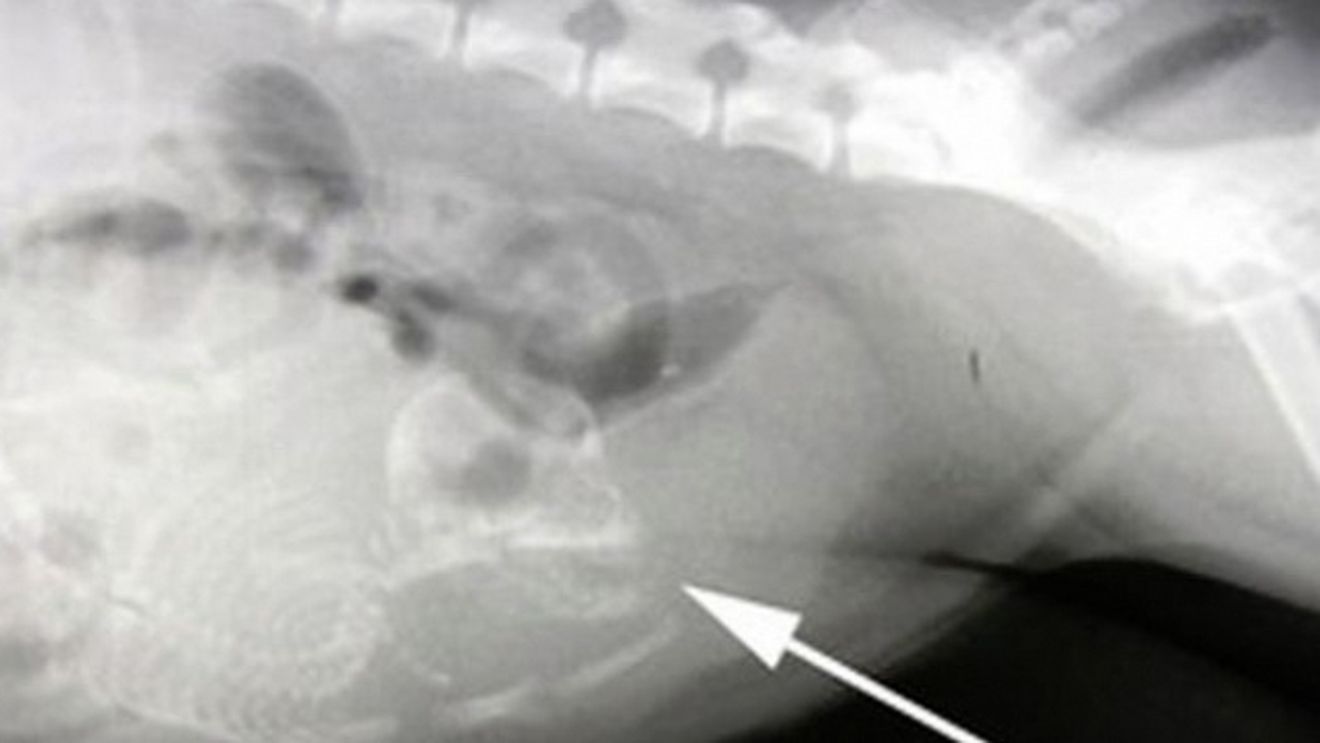

Medicii au vazut pe ecografie ca baiatul avea in corp fetusul nedezvoltat al unui frate geaman. Xiao a fost operat imediat si acum va duce o viata normala.

Baiatul ar fi trebuit sa aiba un farte geaman identic, dar acesta nu s-a mai dezvoltat si a fost pur si simplu „absorbit” in abdomenul lui Xiao.

Daca operatia nu ar fiu fost facuta la timp, baietelul ar fi murit. Fetusul avea aproximativ 25 de cm lungime.